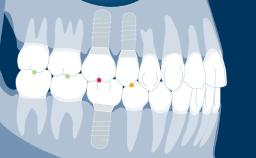

With the introduction of intraoral scanners and the widely used application of implant-supported prostheses produced using CAD/CAM - or Computer-Aided Design/Computer-Aided Manufacturing - it is possible to digitize implant positions directly in the patient's mouth.

Making intraoral scans of implants, rather than digitizing plaster casts based on conventional impressions, saves a number of steps in the restorative process. With fewer steps, there is potentially also less risk of errors and discrepancies. This module will focus on the applications of intraoral scanning of dental implants.